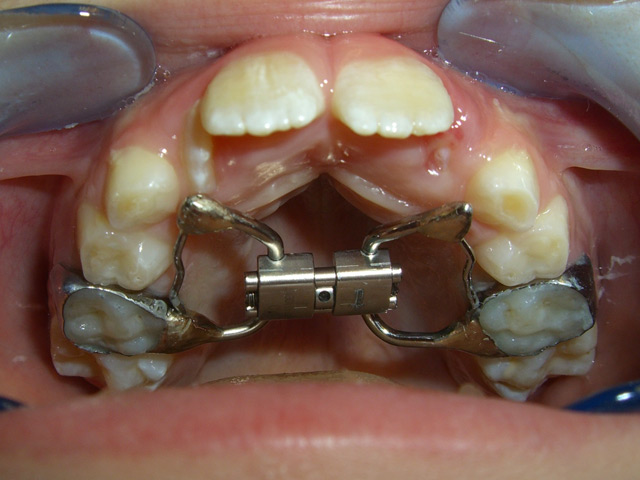

ESPANSORE PALATALE

L'espansore palatale è indicato in caso di insufficienza trasversale superiore (palato ogivale, morso crociato mono e bilaterale).